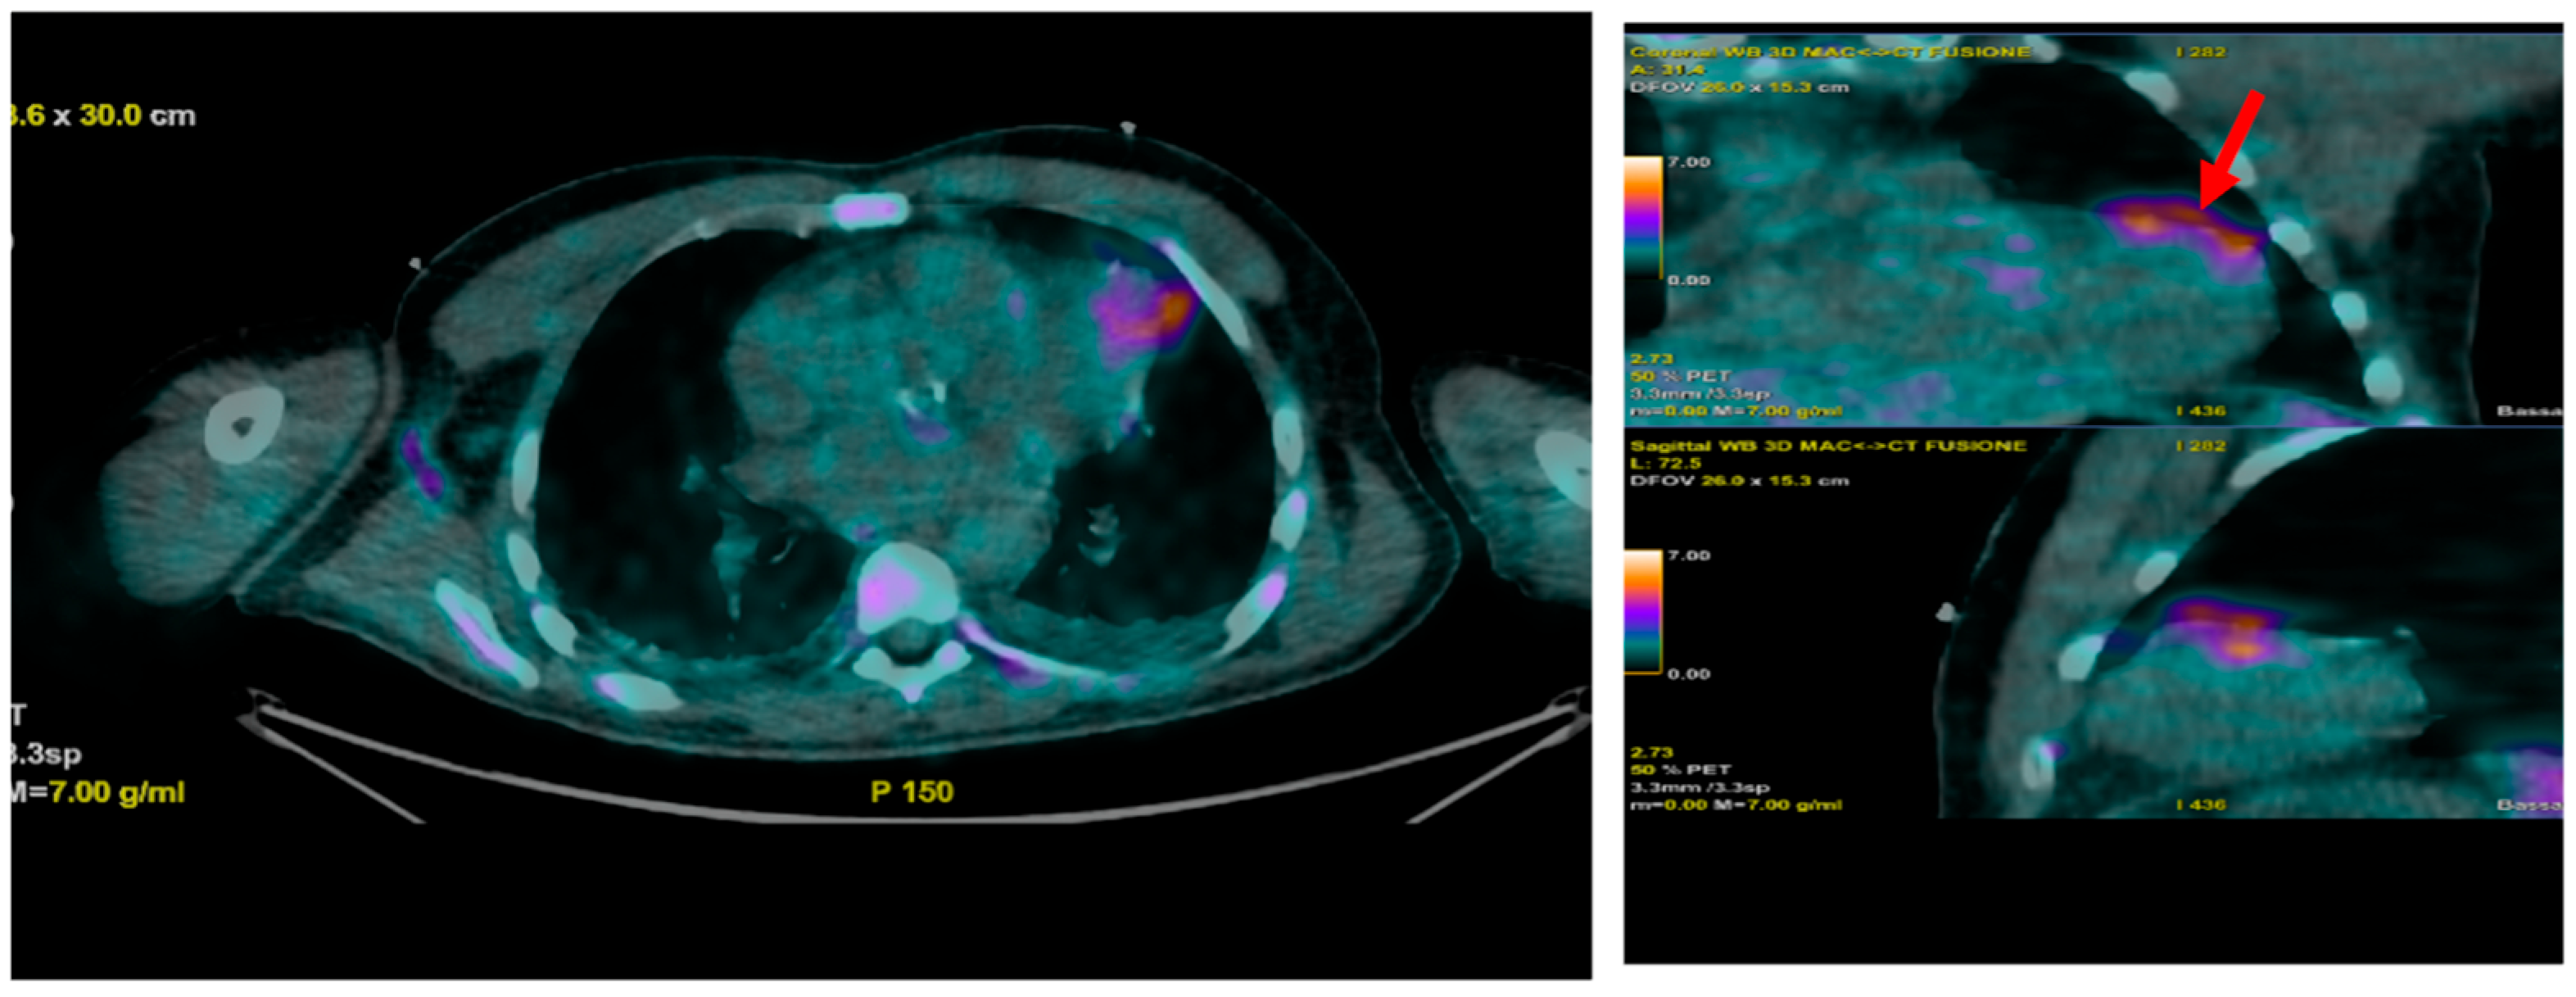

- Prosthetic valve endocarditis (PVE): FDG-PET/CT and WBC scintigraphy are recommended when echocardiography is inconclusive or negative, but clinical suspicion remains high. These modalities are especially valuable for detecting perivalvular infection, invasive complications, and extracardiac septic emboli. Abnormal focal uptake around the prosthesis is considered a significant criterion for PVE diagnosis, and can reclassify cases from “possible” to “definite” IE within the modified Duke criteria framework [13,43,44,45]

- Reclassification from possible to definite IE: The ESC guidelines incorporate abnormal FDG-PET/CT or WBC scintigraphy findings as a significant criterion for IE diagnosis in patients with prosthetic valves or devices. This allows for reclassification of cases initially deemed “possible” IE to “definite” IE when nuclear imaging demonstrates focal uptake consistent with infection, particularly in the setting of non-diagnostic echocardiography or ambiguous clinical findings (Figure 16, Figure 17 and Figure 18) [43,44,46].

- FDG-PET/CT: Sterile post-surgical inflammation can cause increased FDG uptake, leading to false positives and reduced specificity within the first 1–3 months after valve implantation or cardiac surgery. Therefore, caution is advised when interpreting FDG-PET/CT results during this period [18,59]. Moreover, strict patient preparation is required in order to suppress physiological myocardial glucose uptake and improve diagnostic accuracy. A minimum 6 h fast and a low-carbohydrate, high-fat diet prior to imaging is needed, as this reduces background myocardial FDG uptake and enhances visualization of infectious foci. This stringent preparation can be challenging to achieve in acutely ill or diabetic patients, potentially limiting its real-world applicability.